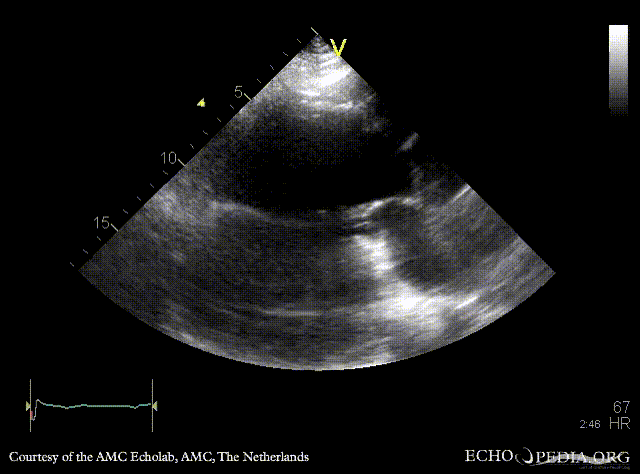

A3CH: large pseudoaneurysm of posterior wall, spontaneous echocontrast A3CH: Color Doppler, severe mitral regurgitation

A2CH: large pseudoaneurysm of posterior wall, spontaneous echocontrast